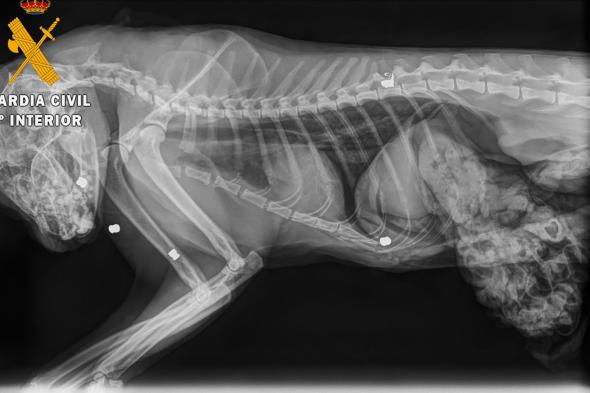

El gato tiroteado, en una imagen difundida por el Seprona de la Guardia Civil.GUARDIA CIVIL

Al cuerpo del gato se le realizó una necropsia en una clínica veterinaria de Estella, donde se determinó que el animal había fallecido por el impacto de cinco perdigones. Se extrajo uno de los cinco proyectiles por si fuese necesario para un análisis.